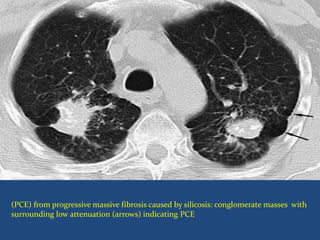

Paracicatrieial Emphysema

 also referred to as irregular or scar emphysema

 Distension and destruction of terminal air spaces adjacent

to fibrotic lesions.

 Causes

Tuberculosis (MC),

silicosis.

 Often associated traction bronchiectasis and honeycomb

lung.

(PCE) from progressive massive fibrosis caused by silicosis: conglomerate masses with

surrounding low attenuation (arrows) indicating PCE